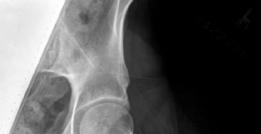

Standard preoperative imaging must include an anteroposterior (AP) pelvis, cross-table lateral, and false-profile view of the affected hip. These evaluate for dysplasia, impingement morphology (cam/pincer), and degenerative changes.

Magnetic Resonance Arthrography (MRA) is the gold standard for evaluating the capsuloligamentous complex. Extravasation of contrast anteriorly often delineates the size and location of the capsular defect. MRA also assesses labral integrity, chondral damage, and the viability of the femoral head. A 3D computed tomography (CT) scan is highly recommended to quantify femoral anteversion and acetabular version, as unrecognized osseous malorientation (e.g., severe femoral retroversion) will predispose the reconstruction to failure if not addressed concurrently with a derotational osteotomy.

Capsulotomy and Joint Evaluation

A Z-shaped capsulotomy is typically performed, though in cases of severe capsular deficiency, the surgeon may encounter a massive defect with dense scar tissue. The remaining capsular edges are tagged with heavy non-absorbable sutures. The hip is dislocated anteriorly by externally rotating and flexing the leg. The ligamentum teres is sharply excised if intact. The femoral head and acetabulum are inspected for chondral defects, and any concurrent intra-articular pathology (e.g., labral tears, cam lesions) is addressed at this stage.